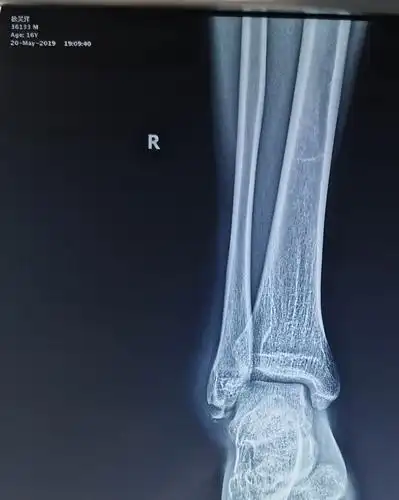

左小腿胫腓骨粉碎性骨折整个历程记录

右侧胫腓骨下段骨折